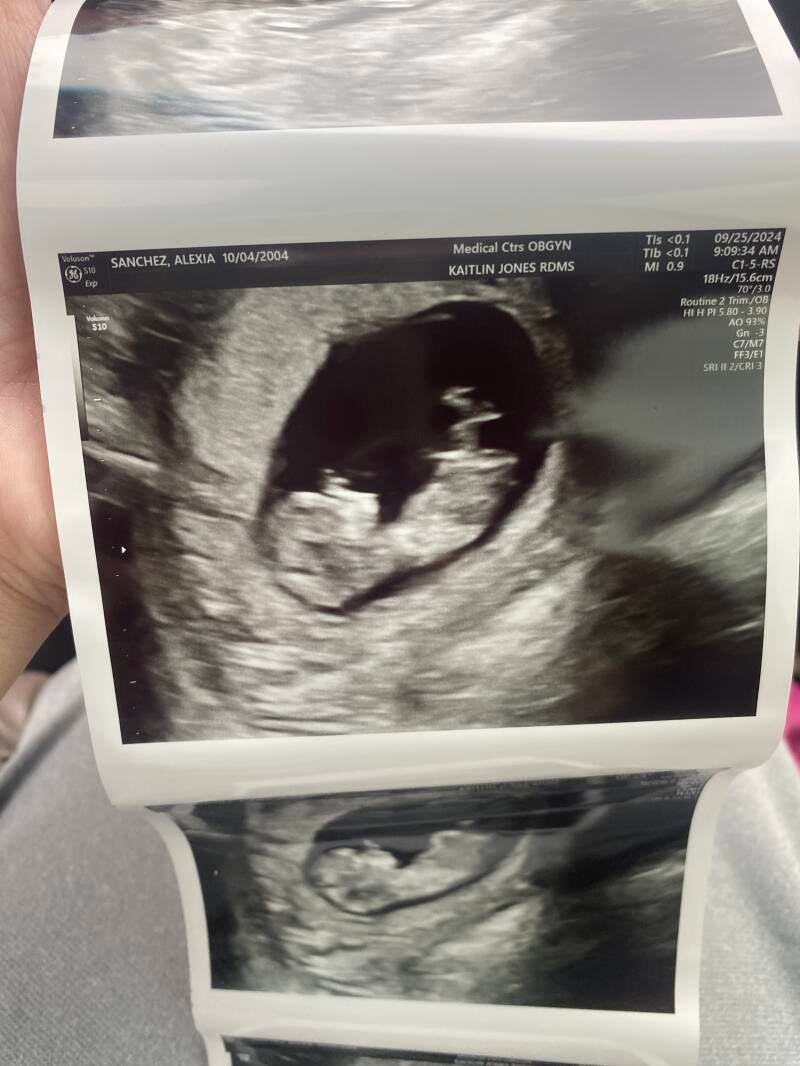

My first doctor's appointment was on September 25, 2024—a moment that truly made everything feel real. We were going to have a baby! The thought of my body nurturing a tiny human, whose life would soon be in our hands, was both overwhelming and exhilarating. I felt an incredible mix of joy and nerves all at once. Seeing her for the first time was absolutely heartwarming. These ultrasound images were taken at 11 weeks and 1 day, and her heartbeat was so strong—169 beats per minute! Everything went perfectly, and it was such a beautiful experience.